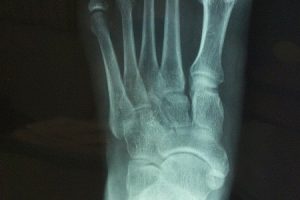

The foot is a complex structure consisting of several small bones, muscles, tendons, and other soft tissues responsible for bearing your weight and helping you navigate the world around …